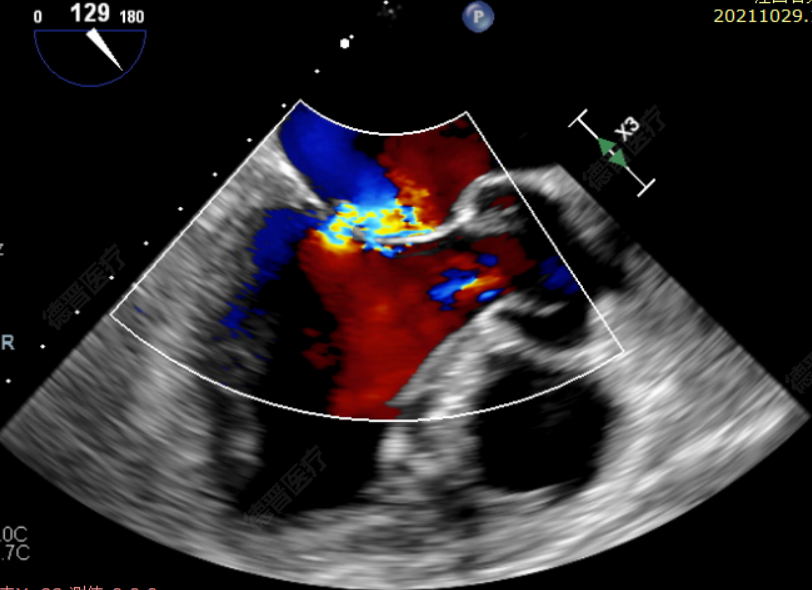

患者一术后超声

患者二术后超声

洪浪院长带领心脏瓣膜团队反复评估患者病情,考虑到患者年龄,手术风险较高,决定采用最优治疗方式,以提升患者术后生活质量。术中,洪浪院长及心脏瓣膜团队在超声和射线引导下经股静脉穿刺房间隔,通过输送系统将器械送入左心房,顺利到达病变区域,在经食道超声及DSA的引导下,成功植入DragonFly瓣膜夹,手术均取得圆满成功。两位患者于术后三天即康复出院,随访无任何不适症状,恢复情况良好。